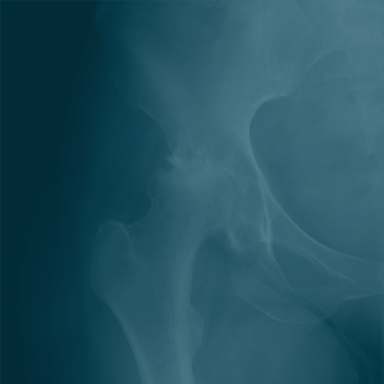

- Chondrosarcoma- cancer that develops in cartilaginous tissue. Cartilage is the material that is layered over bones and joints. This kind of cancer is most often found in the pelvis, upper leg, and shoulder. Chondrosarcoma is commonly found in adults over the age of 40.

- X-rays